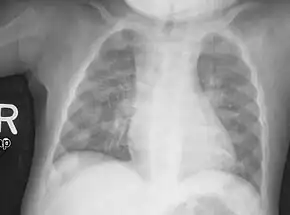

| Rachitic rosary on chest radiograph |

The prominent knobs of bone at the costochondral joints of rickets patients are known as a rachitic rosary or beading of the ribs. The knobs create the appearance of large beads under the skin of the rib cage, hence the name by analogy with the beads of a Catholic Christian rosary.[1]